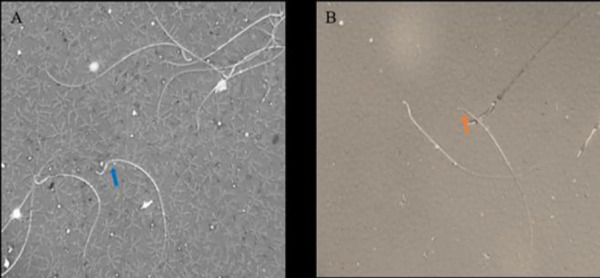

Materials and methods: In this study, forty male rats were classified into the following groups: the control group, the sham group receiving only busulfan carrier solution (DMSO 50%) on days 1 and 21 via intraperitoneal injection, the busulfan group received intraperitoneally 10 mg/kg of busulfan on days 1 and 21, the Aloe group received 25 mg/kg of Aloe-dry juice, and the AF group was administered with 71 mg/kg (containing 25 mg/kg of Aloe dry juice). Treatment was performed by gavage for 56 days. Testis weight and histological alterations, sexual hormone levels (testosterone, estrogen, and progesterone), and classical and functional sperm parameters were examined.

Results: Our findings showed that AF negatively affects testicular tissue architecture and sperm quality such as count, motility, morphology, and viability which were accompanied by an imbalance of testosterone, estrogen, and progesterone hormones. In addition, reaction oxygen species (ROS) and apoptosis increased in the sperm cells of the AF group while decreasing their mitochondrial membrane potential.